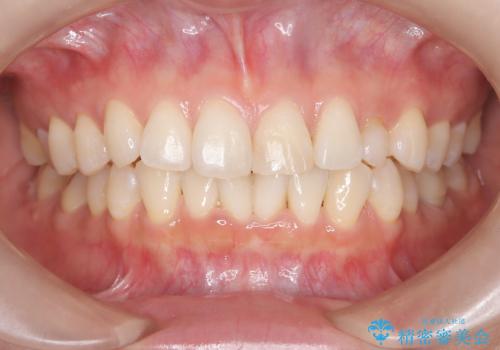

- 20代女性

- 以前に前歯を折れた時、コンポジットレジンで修復したが、変色してきたことを主訴に来院されました。

今回は、セラミッククラウンによる修復を希望され、治療を行っています。